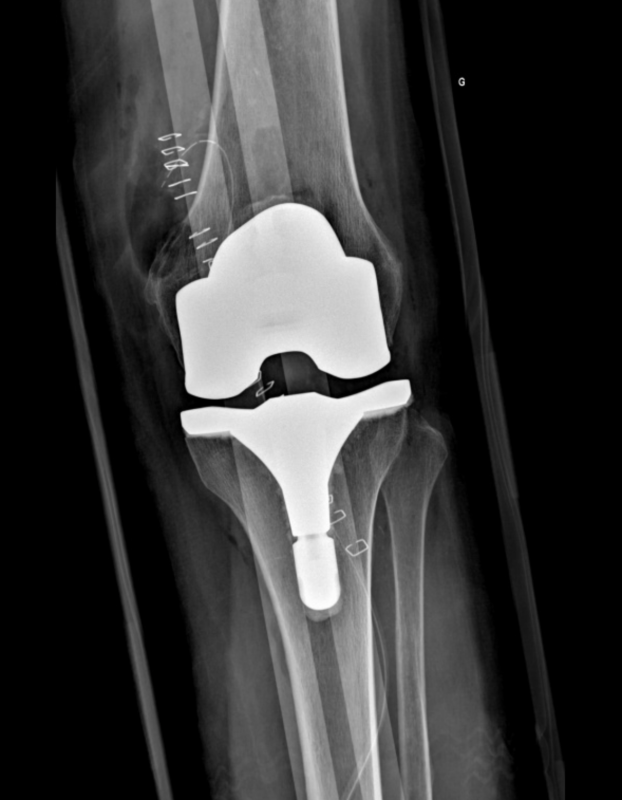

PROTHÈSE DE GENOU NAVIGUÉE EN 3D

résultat final